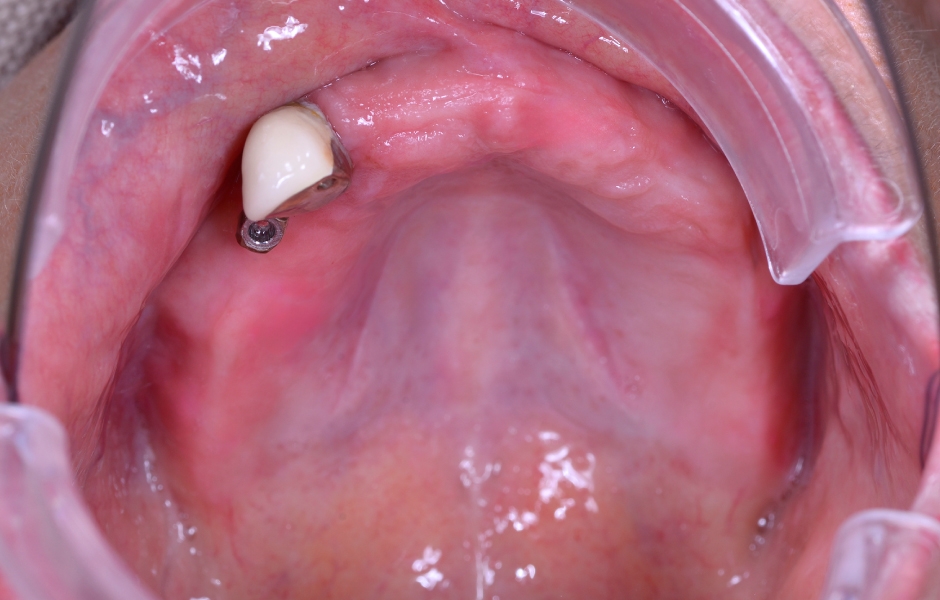

Obr. 1: Klinická a radiologická výchozí situace v horní čelisti se selhávajícími předchozími rekonstrukcemi.

Obr. 2: Klinická a radiologická výchozí situace v horní čelisti se selhávajícími předchozími rekonstrukcemi.

Obr. 3: Klinická a radiologická výchozí situace v horní čelisti se selhávajícími předchozími rekonstrukcemi.

Obr. 4: Klinická a radiologická výchozí situace v horní čelisti se selhávajícími předchozími rekonstrukcemi.

V prezentovaném případě byla k implantoprotetické rehabilitaci odeslána téměř 78letá pacientka, bývalá silná kuřačka. V průběhu let přišla v důsledku generalizované chronické parodontitidy o všechny zuby v horní čelisti, s výjimkou zubu 13, který byl výrazně kompromitovaný, viklavý a bez možnosti záchrany. Pacientka si stěžovala na přetrvávající krvácení, citlivou sliznici horní čelisti a halitózu. Její hlavní prioritou bylo mít „co nejdříve fixní zuby“, aby mohla konečně bez bolesti kousat a usmívat se.

Zároveň si přála krátkou dobu léčby a minimum návštěv vzhledem k dlouhé dojezdové vzdálenosti. Úvodní klinická kontrola prokázala dobře udržovaný redukovaný dolní zubní oblouk. V horní čelisti ale dlouhodobé používání nevyhovující zubní náhrady vedlo k patrnému úbytku kosti. Možnost provedení augmentace kosti v horní čelisti před zavedením implantátů pacientka odmítla jako příliš invazivní a časově náročné. Namísto toho, v závislosti na výsledcích radiologického vyšetření, preferovala okamžité zavedení implantátů s provizorní rekonstrukcí – podle konceptu SKY Fast&Fixed a bez komplexních augmentačních výkonů. Tuto alternativu považovala za variantu s nejlepším poměrem vynaloženého úsilí a přínosu.